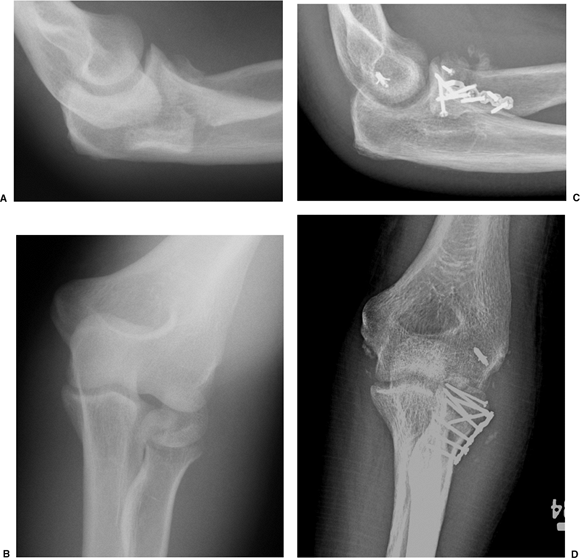

![]() |

|

Figure 9.9. Complex fractures of the entire head are very challenging to repair. A. This patient received a fracture-dislocation while playing hockey. The majority of the radial head is dislocated posteriorly. B. The complexity of the fracture is apparent on the AP radiograph. C.

A 2.0-mm blade plate and screws were used to repair the fracture, which consisted of two large head fragments and substantial metaphyseal comminution. D. The lateral collateral ligament was also repaired. (Copyright © David Ring, MD.) |